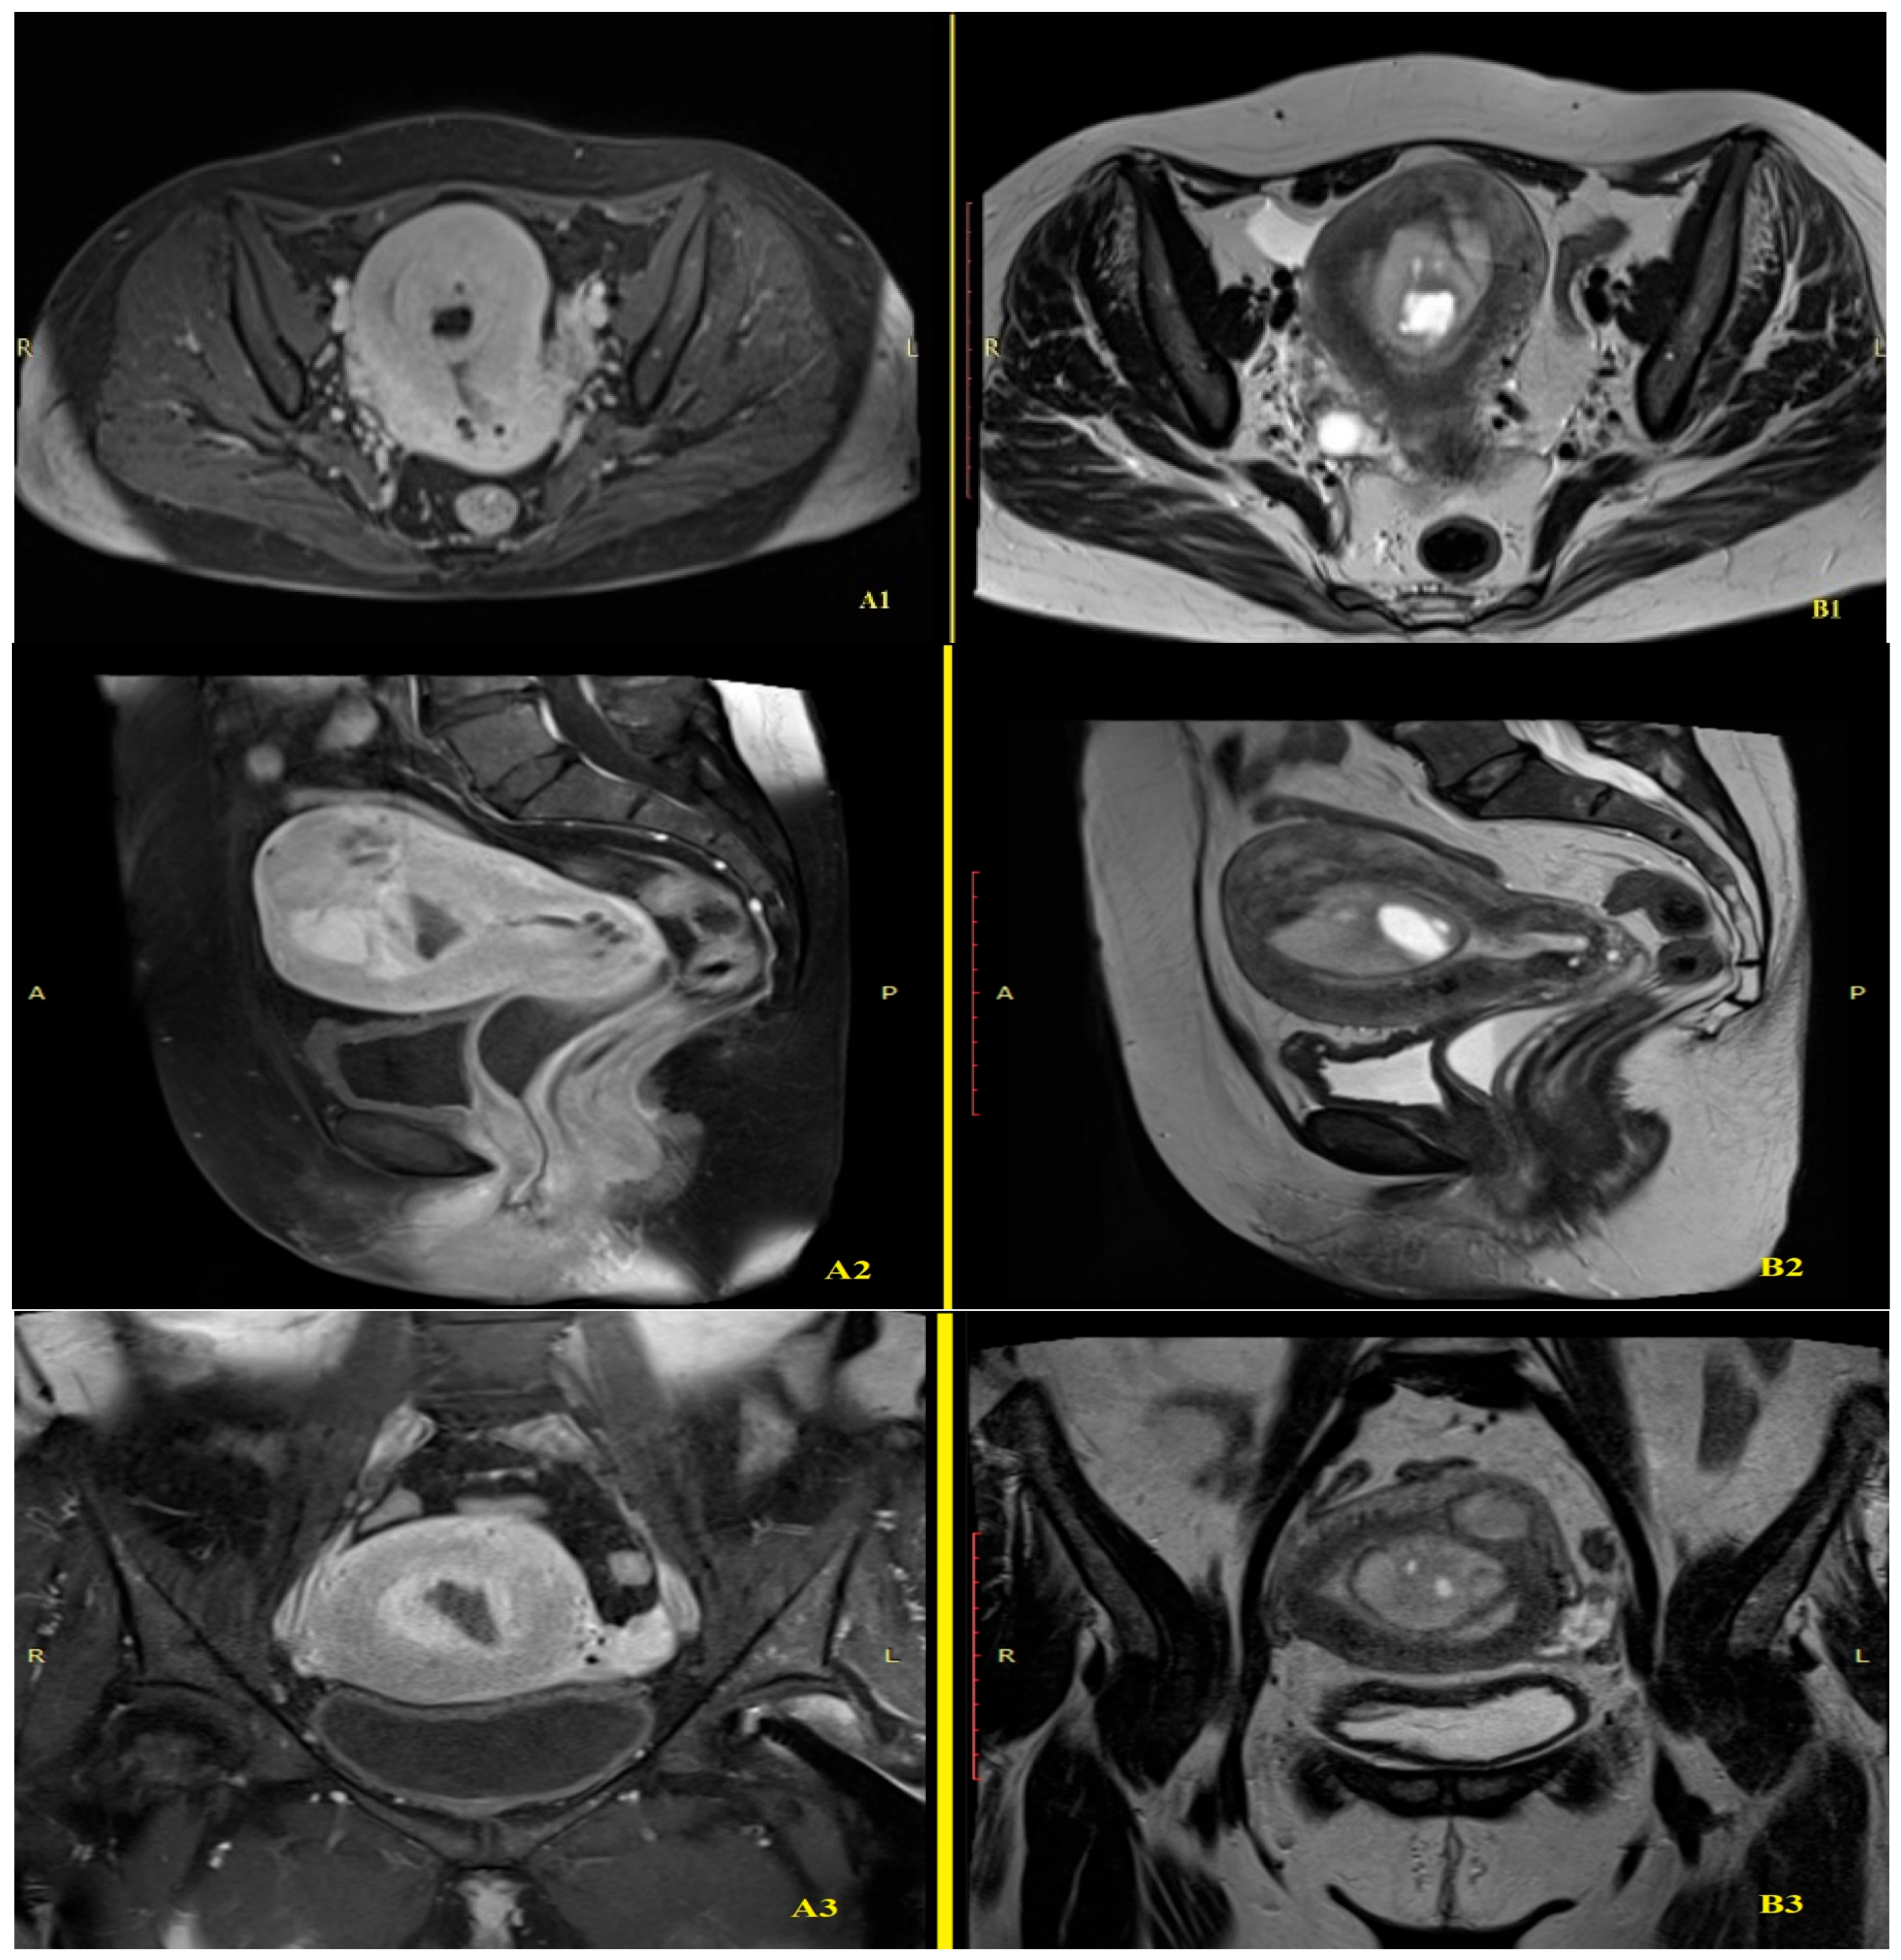

2.2. Imaging Findings

3.4. Imaging and Clinical Presentation